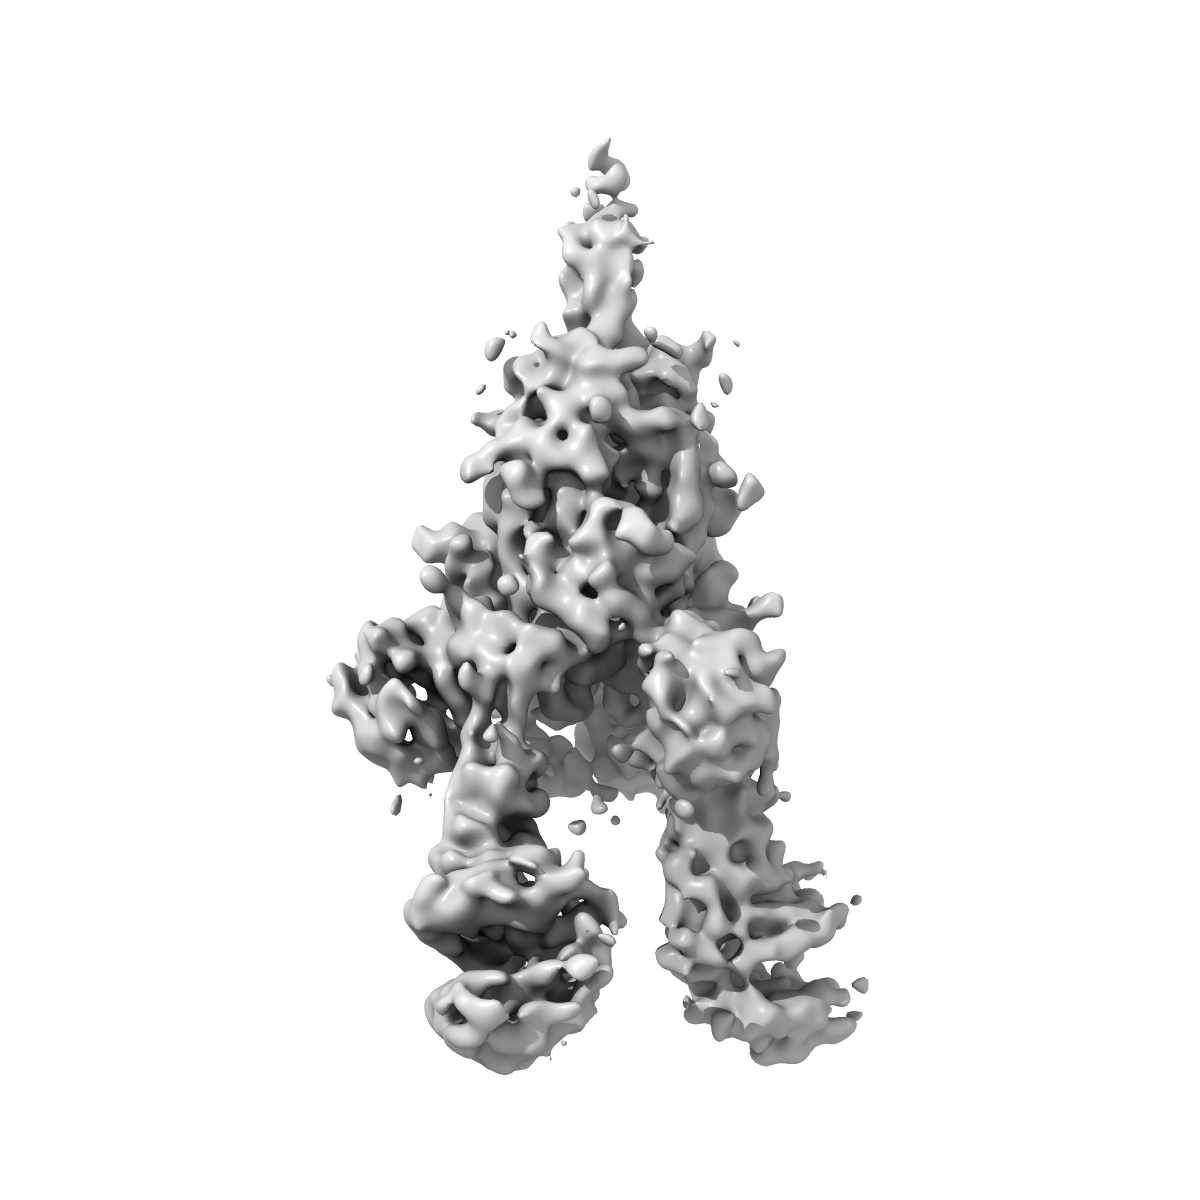

SARS spike glycoprotein, stabilized variant, S1 CTD configurations: ACE2-bound, ACE2-bound, downwards

Sample Organism: SARS coronavirus, Homo sapiens

Sample: SARS Spike Glycoprotein complexed to ACE2 receptor

Deposition Authors: Kirchdoerfer RN, Wang N, Pallesen J, Turner HL, Cottrell CA, McLellan JS, Ward AB

Stabilized coronavirus spikes are resistant to conformational changes induced by receptor recognition or proteolysis.

Kirchdoerfer RN, Wang N , Pallesen J , Wrapp D , Turner HL, Cottrell CA , Corbett KS, Graham BS, McLellan JS , Ward AB

(2018) Sci Rep , 8 , 15701 - 15701

PUBMED: 30356097

DOI: doi:10.1038/s41598-018-34171-7